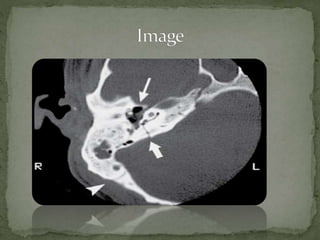

1. Air in Internal Auditory

Canal (thin arrow).

2. Transverse temporal bone

fracture (thick arrow).

3. Normal suture line

between temporal and

occipital bones.

1. Air inInternal Auditory Canal (thin arrow). 2. Transverse temporal bone fracture (thick arrow). 3. Normal suture line between temporal and occipital bones.